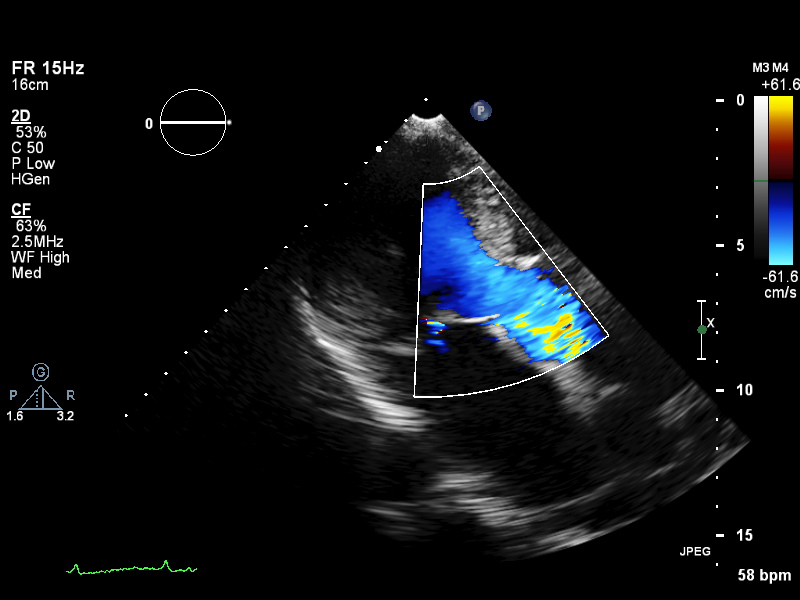

ImageView NameDescription

plax-valves-mv plax-valves-mv PLAX focused on the mitral valve